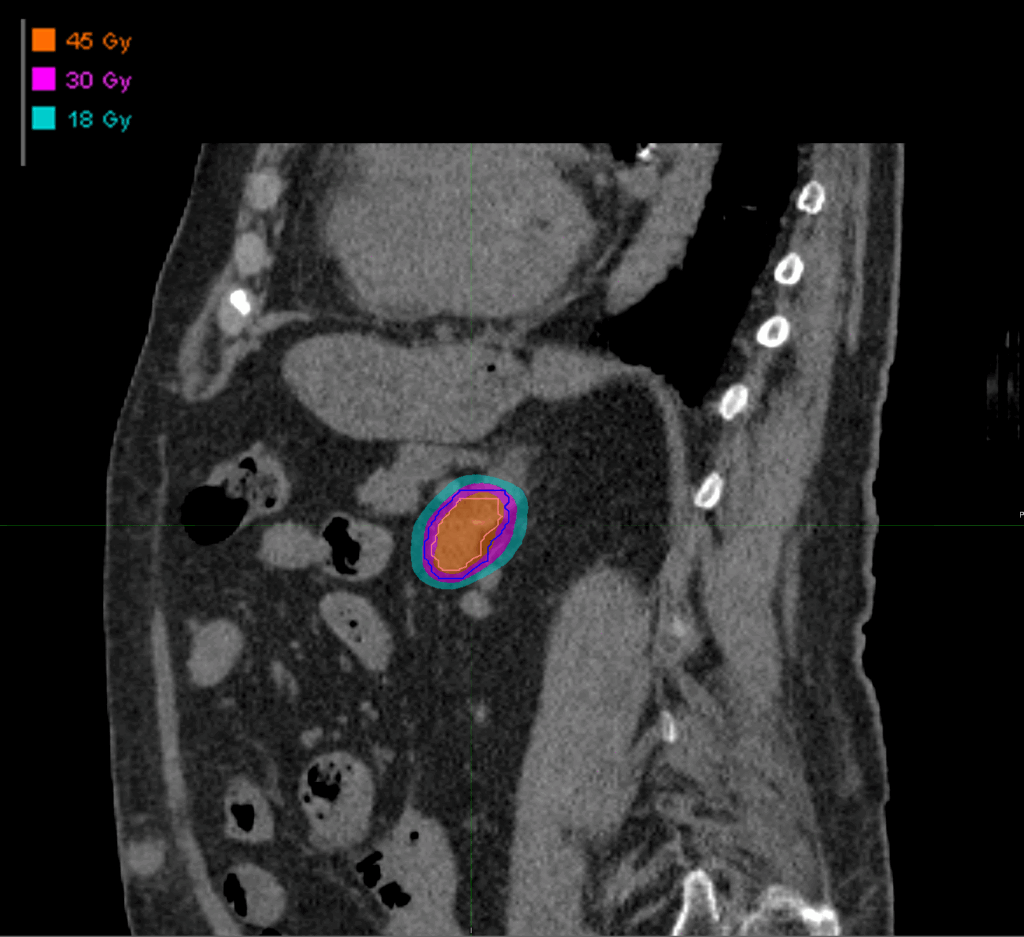

Treatment Plan Images

Fractionation

45 Gy in 3 fractions

PTV(s) Volume

PTV, 14.7 cc

Dose Distributions

- Prescription to the 76.1% isodose line

- Max. dose 59.13 Gy